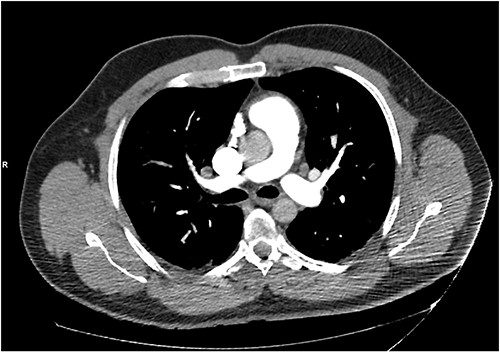

He presented with right sided abdominal pain associated with jaundice, fever, myalgia and arthralgia after receiving his second dose of the penultimate cycle of intra-renal BCG instillation. He did not have any tuberculosis contacts. His parameters on admission were stable. C-reactive protein levels were 230 mg/l and white cell count (WCC) was 6.51 × 109/l. His liver function tests were deranged, with a mixed obstructive and hepatitic picture. A CT kidneys, ureters and bladder (KUB) showed mild diffuse dilatation of the right ureter and renal pelvis with minimal amount of peri-ureteric fat stranding (Fig. 1). A CT scan of the abdomen with intravenous contrast (IV) was performed, this showed a distended right ureter down to the vesicoureteric junction, peri-ureteric fat stranding and lymphadenopathy in the aorto-caval space together with splenomegaly and atelectatic changes (Fig. 2).

A CT scan of the abdomen with IV contrast showed atelactic changes in the lung bases (top left), reactive hilar nodes (top right), a distended right ureter all the way down to the vesicoureteric junction surrounded by fat stranding (bottom left) and splenomegaly (bottom right).